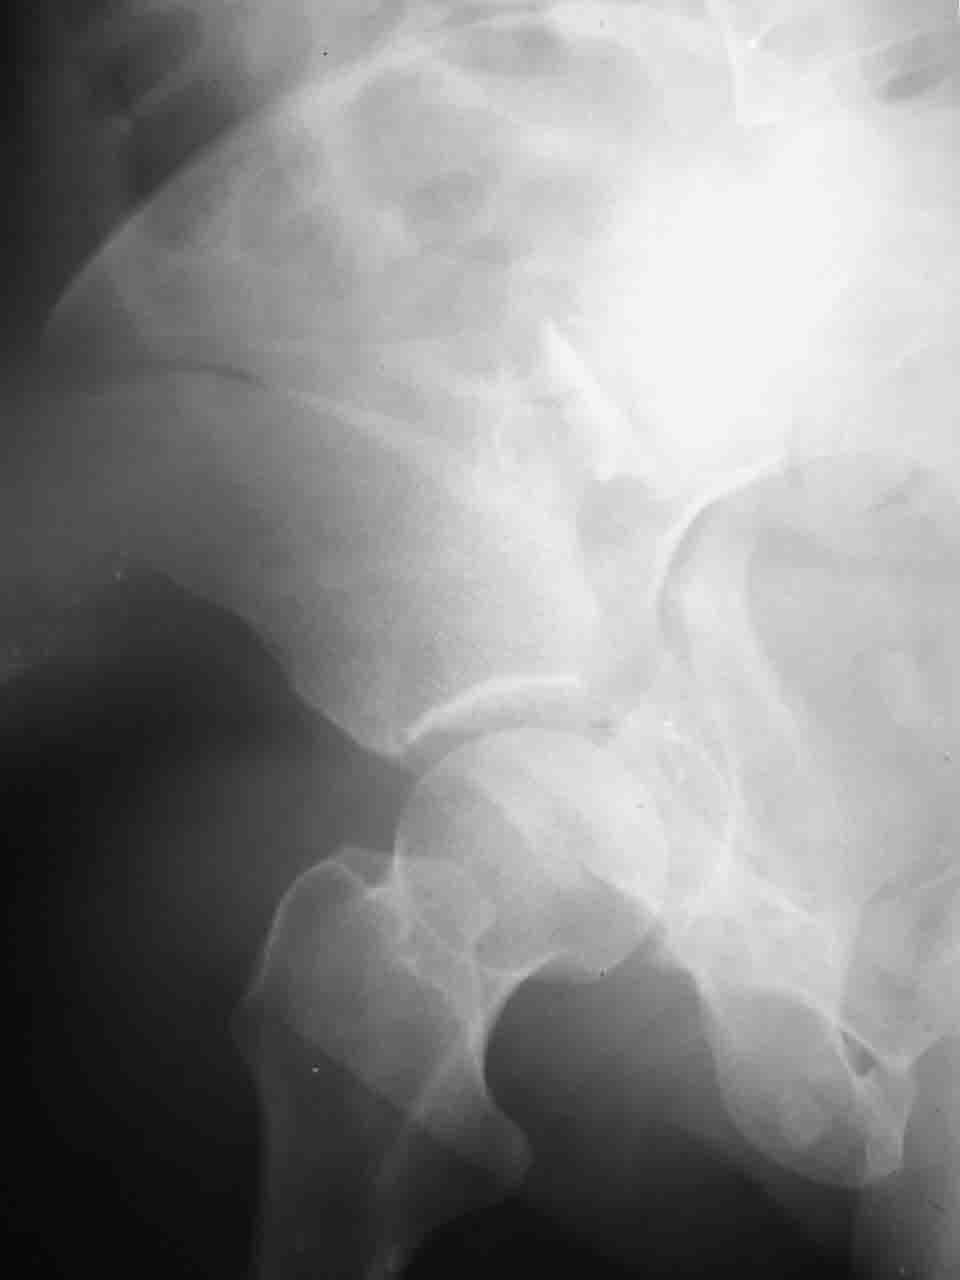

> А какой отдел вертлужной впадины более важен - передний или задний?

Однозначного ответа у меня нет : лучше быть богатым и здоровым , чем бедным и больным :-))

Логика подсказывает, что все-таки лучше иметь анатомически полноценную впадину, хотя ранее упоминалось состояние вторичной конгруэнтности и одно наблюдение у меня есть, когда у больного с полностью нарушенной анатомией впадины и подвывихом головки бедра кзади и кверху боли отсутствовали при относительно достаточном для стиля жизни больного объёме движений. Но это только одно наблюдение и кроме перелома впадины у этогобольного была и тяжелая ЧМТ в анамнезе. Основываясь на формулировке структуры ацетабулюм Э. Летурнеля - как перевернутой буквы Y, впадина для полноценной функции сустава должна иметь сферичность, соответствующую размеру головки бедра и если один из компонентов в дефиците, то функциональные последствия рано или поздно проявятся.

Вопрос доступа к вертлужной впадине при остеосинтезе задача не простая. Конечно, у Летурнеля и Тайла всё давно описано, нам остается только брать на вооружение. Но сами понимаете, что не бывает двух одинаковых ситуаций, поэтому в каждом случае вопрос решается сугубо индивидуально. Наша главная цель - восстановить анатомию с нанесением минимальной дополнительной травмы тазобедреннному суставу, думаю с этим никто не поспорит. Расширенный илиофеморальный доступ уж слишком травматичен (как сказал один коллега "таз лежит отдельно, больной отдельно").Стоит ли делать из пациента анатомический препарат для того чтобы легче ориентироваться. Да и нужно ли собирать всю "мозаику"? Мы применяли при таких операциях своеобразную операционную хитрость - сначала устраняли грубое смещение крыла под гребнем с фиксацией так называемой "плавающей" пластиной (временно фиксированной на двух винтах)- доступ или продлевали боковой, или делали небольшой дополнительный разрез над гребнем. Это позволяло устранить грубое смещение и захождение отломков тела повздошной кости, что значительно облегчало репозицию и остеосинтез впадины над сводом. Основное внимание конечно же уделяли нагружаемому задне-верхнему отделу. Сообщите ваш адрес, пришлю схемы и рентгенограммы.